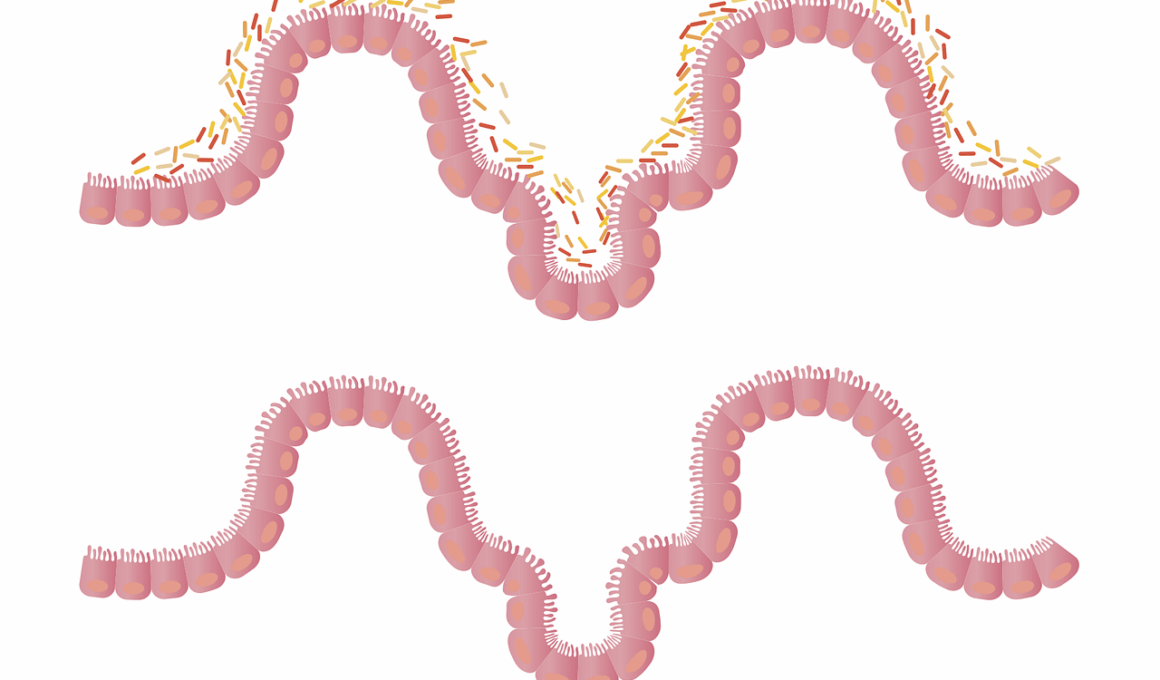

One prevalent myth surrounding vegan diets is that they lead to digestive problems. Many people wrongly assume that a high-fiber diet causes bloating and discomfort. However, introducing fiber gradually helps ease the transition while optimizing gut health. Those who suffer from digestive issues should consider their overall fiber intake instead of blaming plant foods exclusively. Enzymes from certain plant foods, like bananas or kiwis, can aid digestion, allowing individuals to consume larger quantities of fibrous plants. Additionally, an undeveloped understanding of gut microbiota often results in misconceptions about plant-based eating. Research shows that various plant-based foods contribute positively to gut microbiomes, promoting diversity in gut bacteria. A diverse microbiome can enhance nutrient absorption, immune system function, and mood regulation. Athletes often worry that a diet lacking animal products impairs performance; this is untrue when carefully balanced. Sourcing nutrients from whole food sources, such as whole grains, legumes, nuts, and seeds, ensures a well-rounded diet. Consuming fermented plant foods, like kimchi or sauerkraut, further supports gut health by introducing probiotics. Awareness of how to maintain gut health on a vegan diet is essential for athletic success.

Another critical element for effective vegan gut health is dietary diversity. Many believe that sticking to a few core foods can meet their nutritional needs; this is misleading. Embracing a wide range of plant foods and experimenting with new ingredients keeps meals exciting while ensuring all nutrient bases are covered. Adding variety also introduces beneficial phytochemicals, vitamins, and minerals that promote optimal gut function. Seasonal produce can inspire creativity in meal planning while offering diverse nutrient profiles. Additionally, exploring cuisines from around the world can enrich a vegan diet; adopting spices and herbs often found in global recipes adds another layer of flavor and health benefits. Choosing various textures and colors enhances visual appeal and health benefits. Colorful vegetables and fruits often represent different phytonutrients, providing antioxidants that support gut health and overall well-being. This variety creates a balanced intake of essential nutrients while reducing the risk of dietary boredom. Connection with food sources is essential as well; local or organic produce can accentuate flavors while enhancing nutrient density. Consuming a variety of vegan foods supports gut health, development, composition, and diversity of the microbiome effectively.